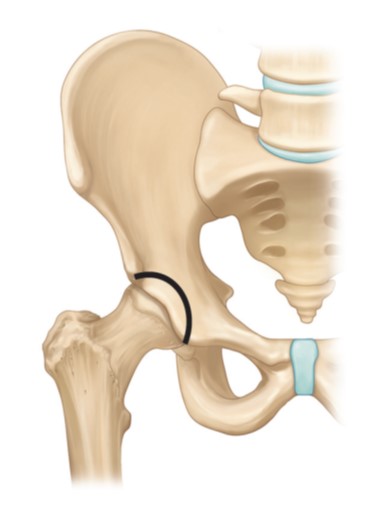

고관절 이형성증 : 비구 성형술 (비구 절골술)

고관절 이형성증이란 출생시부터 발생한 고관절 비구 부분의 발육저하로 인해, 성장에 따라 대퇴골두를 덮고 있는 비구 부분에 결손이 발생하는 질환으로 추후 고관절 관절염의 주요한 원인이 될 수 있습니다. 특히 서구권에 비해 국내에서 그 빈도가 높습니다.

대부분의 병원에서 이에 대해 인공관절 수술을 권유하나, 관절염이 진행하기 전 질병의 초기에 적절한 진단을 한다면, 환자 본인의 관절을 유지하면서 비구를 적절한 형태로 성형하는 방법으로 질병의 진행을 막을 수 있습니다.